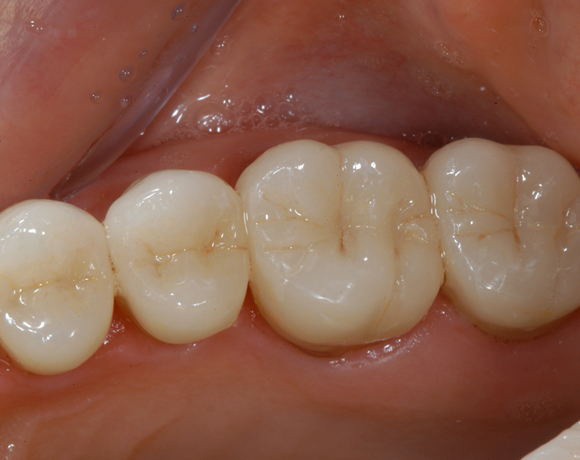

22 Einzelkronen mit Eris for E II

Empress II Presskeramik mit Eris Verblendkeramik bei einer Neuversorgung im Oberkiefer komplett und im Unterkiefer Vollkronen auf den Seitenzähnen.

Ein Projekt aus dem Jahr 2004

Hier wurden der ganze Oberkiefer und die Seitenzähne im Unterkiefer mit neuen Kronen aus Empress 2 und mit Eris Verblendkeramik versorgt.